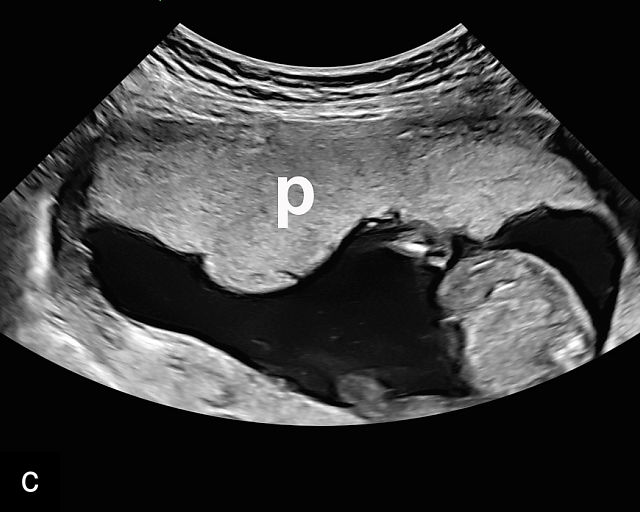

In the early first trimester, trophoblastic tissue appears as an echogenic ring encircling the gestational sac (Figure 1a). By the late first trimester, the placenta becomes recognizable as a distinct structure on ultrasound (Figure 1b). Initially, it presents as a homogeneous echogenic mass (Figure 1b–d) but undergoes progressive differentiation, becoming more heterogeneous as pregnancy advances from the second to third trimester (Figure 1e–g). By the third trimester, cotyledons become discernible, and in the late third trimester, calcifications frequently appear basally and around the cotyledons (Figure 1g).

1

Ultrasound images of development of the placenta (P/p). (a) Trophoblastic tissue appearing as an echogenic ring surrounding the gestational sac at 6 weeks' gestation. (b) Placenta at 12 weeks has become a discrete, uniformly echogenic mass. (c) Placenta at 17 weeks. (d) Placenta at 20 weeks. (e) Placenta at 27 weeks. (f) Placenta at 33 weeks. Increasingly, differentiation and heterogeneous appearance is seen, with demarcation of the cotyledons. Basal calcifications are beginning to appear. (g) Placenta at 40 weeks, showing a distinctly heterogeneous appearance, with clear demarcation of the cotyledons and presence of calcifications.